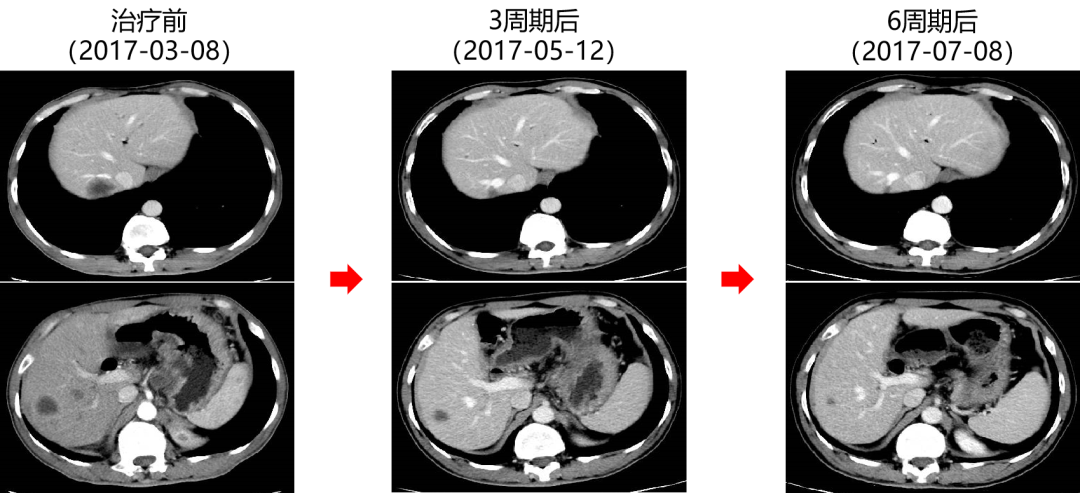

二 病例分享 专家简介 01 基本情况 患者:汪XX,男,63岁。身高 165cm;体重 65kg;体表面积 1.70m2;ECOG 1分。 主诉:反复解黏液血便3天。 对磁共振造影剂过敏,无食物、其他药物过敏史。既往史、个人史、婚育史、家族史均无特殊,无吸烟、饮酒史。 02 初诊病史 现病史:患者2017年3月初无明显诱因下解黏液血便,量中等,为鲜血,反复发作,无恶心、呕血、黑便、腹痛、腹泻、里急后重等不适。遂于2017年3月初就诊我院。 胸、腹、盆腔CT平扫+增强:乙状结肠肠壁明显增厚,肠腔狭窄,增强期强化明显;肝脏多发低密度病灶,增强期不规则强化,考虑乙状结肠癌伴肝脏多发转移。 03 治疗方案 【一线治疗】 2017-06-22 西妥昔单抗+FOLFIRI* Q2W×3 西妥昔单抗 900mg ivgtt D1; 5-氟尿嘧啶 0.6g iv D1,3.5g civ 48h; 亚叶酸钙 0.6g ivgtt D1; 伊立替康 280mg ivgtt D1。 第1疗程结束后黏液血便较前消失,过程顺利,耐受良好,无皮疹、腹泻等不良反应,治疗10疗程,疾病进展。 疗效评估-影像学(部分缓解,PR)。 2017-07-15 乙状结肠癌切除术* 手术记录:肿瘤位于乙状结肠,大小约4cm×3cm,未突破浆膜层,病灶周围可及数个稍肿大淋巴结,未及盆底种植结节。 手术过程顺利,术后恢复良好。 术后病理:(乙状结肠)中分化腺癌,浸润肠壁浆膜下层,两切缘阴性,未见脉管癌栓及神经束侵犯,LN 2/18(+) 2017-08-20 肝转移瘤切除术* 手术记录:肝脏肿瘤位于肝右叶,大小分别约2cm×1.5cm,1cm×1.2cm,其余肝表面未见异常结节,腹腔无腹水、无粘连。 手术过程顺利,术后恢复良好。 术后病理:(肝右叶病灶)中分化腺癌,结合临床病史,符合乙状结肠癌肝转移,肝组织切缘未见癌。 疗效评估-影像学(NED)。 2017-11-06 西妥昔单抗+FOLFIRI* Q2W×3 西妥昔单抗 900mg ivgtt D1; 5-氟尿嘧啶 0.6g iv D1,3.5g civ 48h; 亚叶酸钙 0.6g ivgtt D1; 伊立替康 280mg ivgtt D1; 过程顺利,无皮疹、腹泻等不良反应。每疗程后均予PEG-CSF预防性升白,耐受良好。 疗效评估-影像学(病情进展,PD1)。 胸、腹、盆腔CT平扫+增强:肝左外叶低密度灶,增强期不规则强化,结合病史,考虑结肠癌肝转移,余未见明显异常。 【二线治疗】 2018-03-06 肝左外叶肿瘤切除术* 术中探查见:肿瘤位于肝左外叶,质硬,边界不清,余肝脏表面未见异常结节灶,腹盆腔无腹水。 手术过程顺利,术后恢复良好。 术后病理示:(肝左叶)中分化腺癌,结合临床病史,符合结肠腺癌肝转移。 2018-04至2018-07 卡培他滨+奥沙利铂* Q3W×5 卡培他滨 1.5g BID D1-14; 奥沙利铂 200mg ivgtt D1。 过程顺利、耐受良好,无腹泻、神经毒性等不良反应。 疗效评估-影像学(病情进展,PD2)。 胸、腹、盆腔CT平扫+增强:肝尾状叶结节状异常密度灶,增强期不规则强化,结合病史,考虑结肠癌肝转移,余未见明显异常。 2018-07至2020-04 贝伐珠单抗+卡培他滨* Q3W×21 贝伐珠单抗 500mg ivgtt D1; 卡培他滨 1.5g BID D1-14。 过程顺利、耐受良好,期间曾出现II度腹泻,对症治疗后可恢复正常。无血压升高、出血、蛋白尿、手足皮肤反应。 疗效评估-影像学(最佳疗效,PR)。 疗效评估-影像学(病情进展,PD3)。 腹腔镜肝尾状叶切除术+腹腔粘连松解术* 术中探查见:肿瘤位于肝尾状叶,质硬,边界不清,余肝脏表面未见异常结节灶,腹盆腔无腹水。 手术过程顺利,术后恢复良好。 术后病理示:(肝尾状叶)中分化腺癌,结合临床病史,符合结肠腺癌肝转移。 2020-06至2021-09 贝伐珠单抗+卡培他滨* Q3W×16 贝伐珠单抗 500mg ivgtt D1; 卡培他滨 1.5g BID D1-14。 过程顺利、耐受良好,期间曾出现II度腹泻,对症治疗后可恢复正常。无血压升高、出血、蛋白尿、手足皮肤反应。 疗效评估-影像学(NED)。 疗效评估-影像学(NED)。 【三线治疗】 2021-12-16 西妥昔单抗+TAS-102* Q3-4W×2 西妥昔单抗 900mg ivgtt D1; TAS-102 60mg BID D1-5,8-12。 过程顺利、耐受稍差,期间出现II度骨髓抑制(三系减少),对症治疗后可恢复正常。无皮疹、输液反应等。 疗效评估-影像学(部分缓解,PR)。 04 治疗小结